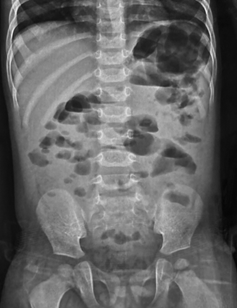

In paralytic ileus, there is too much gas in both small and large bowels (Figure 4 & 5).

Figure 4 Anteroposterior supine abdominal radiograph in a 4-year-old child showing multiple dilatated bowel loops scattered throughout the abdomen haphazardly with presence of gas in the rectum suggestive of paralytic ileus.